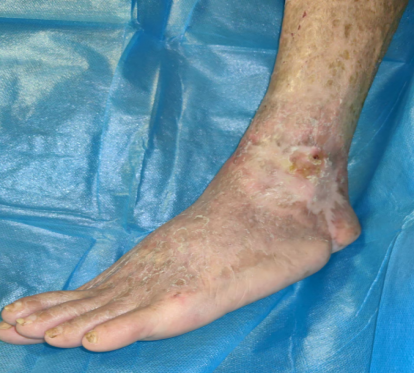

治療下肢缺血性疾病-側方骨膜牽張技術

糖尿病足的特色治療—Masquelet技術+側方骨膜牽張技術+NPWT+HADM聯合自體薄層皮“一步法”復合移植技術

下肢動脈閉塞癥—潰瘍、骨髓炎(保趾成功)NPWT+雙層人工真皮再生修復技術

難治性創面特色濕潤愈合治療技術